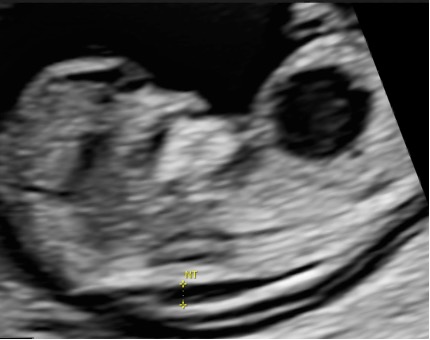

Caso 1

quesito casodelmeseMarzo2026SIEOG